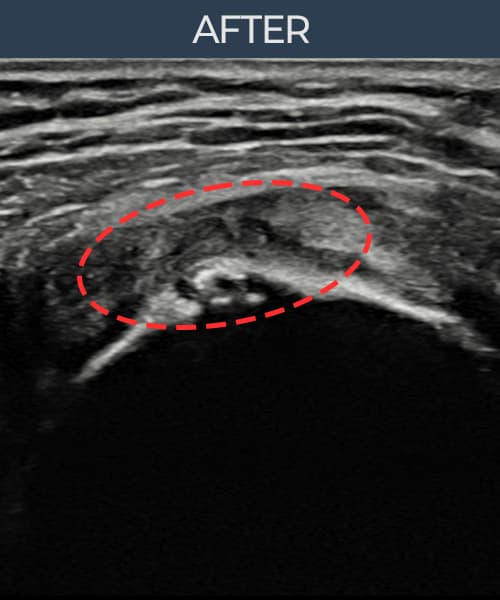

[経過期間: 23.07.31~23.09.27]

[縫縮術] 超音波検査にて左 棘上筋腱 부착부 광범위 部分断裂(13mm × 5mm (腱厚の約65%欠損))を確認。縫縮術施行後、腱の連続性が回復し、日常生活に復帰されました。